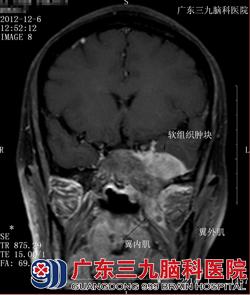

图五 图六

图五、图六:轴位于冠状位T1WI+C:病变包括颅底骨质呈明显强化,病变累及左侧翼内、外肌。